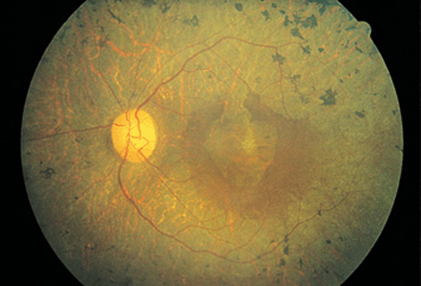

FIGURE 21-4

Retinal vasculitis, uveitis, and hemorrhage in a 32-year-old woman with Crohn’s disease. Note that the veins are frosted with a white exudate. Visual acuity improved from 20/400 to 20/20 after treatment with intravenous methylprednisolone.